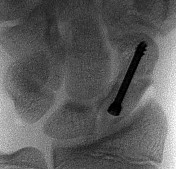

- الأشعة السينية (X-rays): هي الخطوة الأولى في تقييم الكسور، الخلوع، وتغيرات التهاب المفاصل. تساعد في تحديد مدى تدهور العظام والمسافات المفصلية. على سبيل المثال، تُظهر صور الأشعة السينية كسور السلاميات

أو كسور قاعدة العظم المشطي الخامس

، بالإضافة إلى علامات مثل "الدمعة الشعاعية" (Radiographic Teardrop) في الرسغ التي تمثل الزاوية الزندية الراحية الحرجة للكعبرة البعيدة

. - الأشعة المقطعية (CT Scan): توفر صوراً تفصيلية ثلاثية الأبعاد للعظام، وهي مفيدة جداً لتقييم الكسور المعقدة، مثل كسور العظم الخطافي (Hamate Hook Fracture) التي قد لا تظهر في الأشعة السينية العادية

، أو لتقييم مدى تدهور العظم في حالات مثل مرض كينبوك. - التصوير بالرنين المغناطيسي (MRI): ممتاز لتقييم الأنسجة الرخوة مثل الأربطة، الأوتار، الأعصاب، والعضلات. يكشف عن التمزقات،